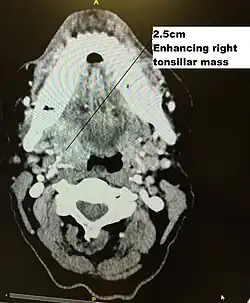

Staging is generally by the UICC/AJCC TNM (Tumour, Nodes, Metastases) system.[68] Staging is based on clinical examination, diagnostic imaging, and pathology. On imaging, involved lymph nodes may appear cystic, a characteristic of HPV+OPC.[69]

HPV+OPC has been treated similarly to stage-matched and site-matched HPV-unrelated OPC. Its unique features, which contrast with smoking-related HPV-OPC head and neck cancers, for which patients' demographics, comorbidities, risk factors, and carcinogenesis differ markedly, suggest that a distinct staging system be developed to more appropriately represent the severity of the disease and its prognosis.[70] Standard AJCC TNM staging, such as the seventh edition (2009),[71] while predictive for HPV-OPC, has no prognostic value in HPV+OPC.[72][73][67][74] The 8th edition of the AJCC TNM Staging Manual (2016)[75] incorporates this specific staging for HPV+OPC.[76] As of 2018, treatment guidelines are evolving to account for the different outcomes observed in HPV+OPC. Consequently, less intensive (de-intensification) use of radiotherapy or chemotherapy,[77] as well as specific therapy, is under investigation, enrolling HPV+OPC in clinical trials to preserve disease control and minimise morbidity in selected groups based on modified TNM staging and smoking status.[78][79][80][81][82]